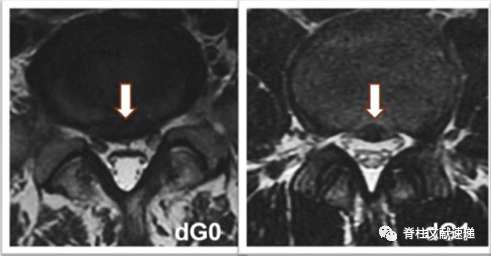

0级:椎间盘与神经根(nG0)或硬膜囊(dG0)之间存在空间;

1级:椎间盘与神经根接触但未受压(nG1),或硬膜囊受压<椎管的1/3(dG1);